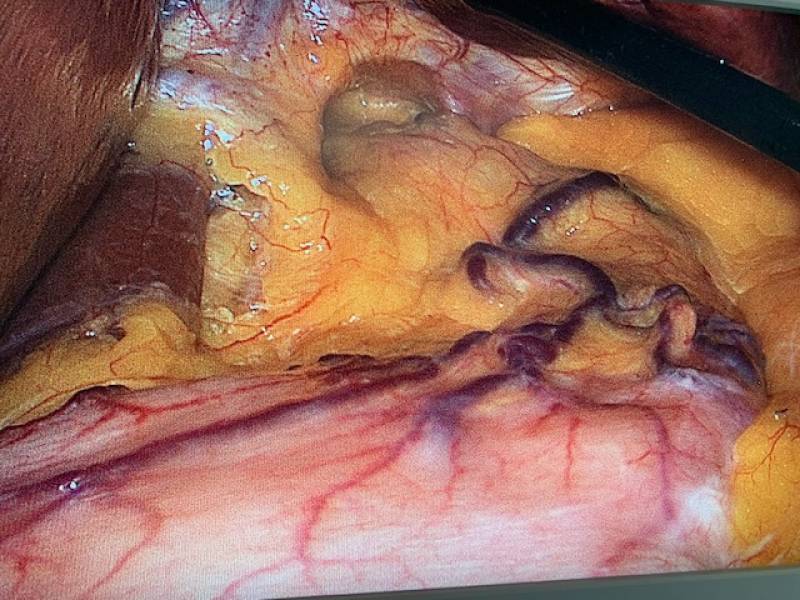

Traitement chirurgical du RGO après sleeve

Quelle solution en cas de reflux après sleeve ?

L'apparition d'un reflux après sleeve peut s'expliquer par: La tubulisation de l'estomac par la résection de la grosse tubérosité gastrique et la section du ligament suspenseur de la grosse tubérosité. la section partielle du sphincter intérieur de l'oesophage l'hyperpression intra-gastrique ...